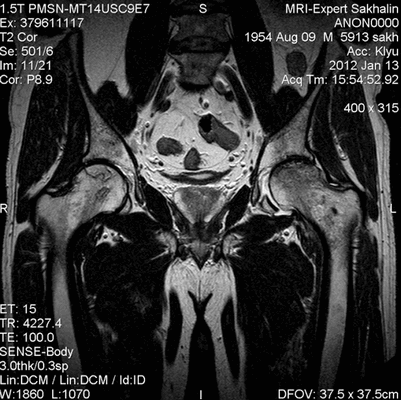

Рисунки 1,2. МР-картина артроза тазобедренных суставов с наличием отека костного мозга дистрофического характера в верхне-наружных отделах вертлужной впадины справа